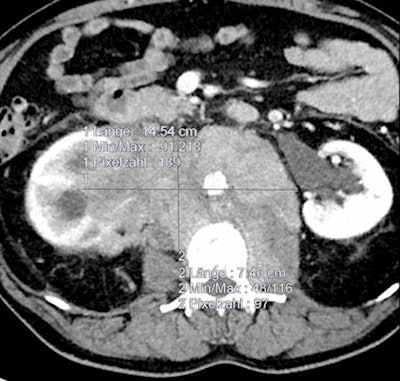

In an attempt to determine whether automated tumor volumetry was necessary or if tumor lesion volume estimates were sufficient, researchers studied 20 patients as part of the two-armed, randomized, phase II multicenter CIOX trial on metastatic colorectal cancer.

In these 20 patients there were a total of 151 target lesions, including:

- Liver: 137 (90.7%)

- Lung: Four (2.6%)

- Lymph node: Six (4%)

- Abdominal wall: Two (1.3%)

- Adrenal gland: Two (1.3%)

Semiautomated volumetry using a commercially available system and manual measurements of the longest RECIST 1.1 diameter and longest orthogonal diameter were performed. When comparing the manual measurements, the researchers found that simulating volume by extrapolating RECIST-based measurements would systematically overestimate tumor volume. However, volume simulations would be relatively accurate based on the World Health Organization (WHO) tumor burden criteria, Graser said.